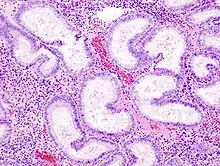

Adénocarcinome endométrioïde, vue d'une biopsie. Coloration HE.